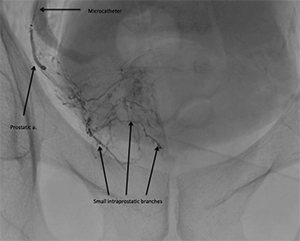

Figure 1

PAE is performed through a small incision in the upper thigh or wrist to gain access to your body's blood vessels (arteries). Through the access site, a soft, steerable catheter is advanced into the arteries that supply the pelvic organs. Angiography is performed, providing the interventional radiologist with a roadmap of the pelvic vessels. See Figure 1 to the left.